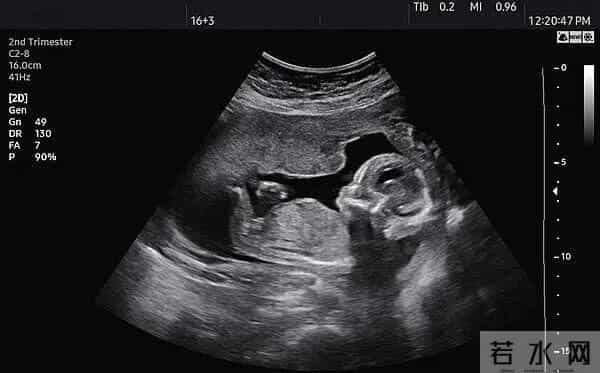

想给娃留张“0岁照片”,结果可能把娃置于辐射风险?2025年6月,国家卫健委一纸新规把“胎儿摄影”直接拖进医美严管区:拍B超留念也得有《医疗机构执业许可证》,拍的人必须是医师或超声技师。

机器没备案、操作员没资质,能量档位随手拧,多扫十分钟,胎儿组织温度悄悄升高。

真要给娃留纪念,正规医院产筛时顺带刻张光盘足够。

别拿微商链接里的“四维写真”当仪式感,那可能是二手翻新机,探头老化、输出超标,风险全由孕妇和胎儿买单。